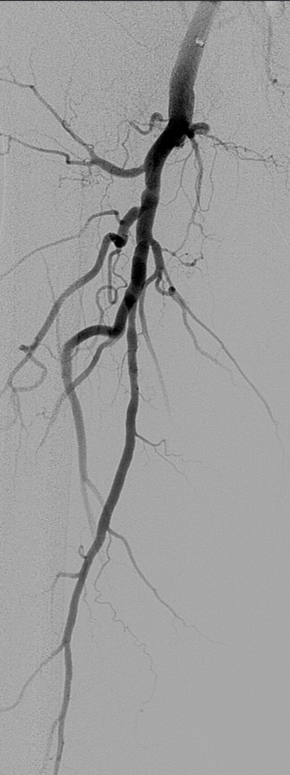

★ Case 5

Female,82 y

Severe claudication over 1 year in both extremities esp. in the left

DM over 10 years

CTA:SFA-PA long CTO

左右滑动查看